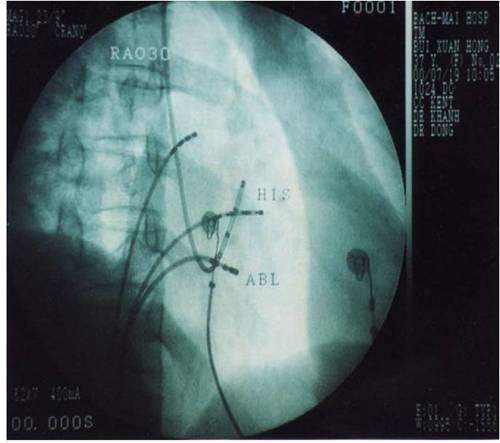

Kỹ thuật triệt đốt đường dẫn truyền phụ dựa trên việc đưa đầu ống thông đốt tới tiếp xúc với một điểm trên vòng van hai lá hoặc ba lá nơi có đường dẫn truyền phụ đi qua. Tiếp cận vòng van ba lá bằng đường tĩnh mạch đùi, tiếp cận vòng van hai lá bằng đường ngược dòng động mạch chủ qua động mạch đùi hoặc qua đường xuyên vách liên nhĩ. Đường dẫn truyền phụ được định vị (mapping) dựa vào các điện đồ trong buồng tim trong lúc nhịp xoang, trong lúc cơn tim nhanh vào lại nhĩ thất hoặc trong lúc tạo nhịp thất và dựa vào hỉnh ảnh giải phẫu trên X quang.

Hình 7: Vị trí các ống thông trên hình ảnh X quang trong triệt đốt đường dẫn truyền phụ: NP: điện cực cùng cao nhĩ phải, His: điện cực vị trí bó His, XV: điện cực xoang vành, TP: điện cực mỏm thất phải, Abl: điện cực triệt đốt được đưa vào thất trái ngược chiều qua van động mạch chủ và cắm vào vòng van hai lá nơi có đường dẫn truyền phụ nhĩ-thất đi qua.